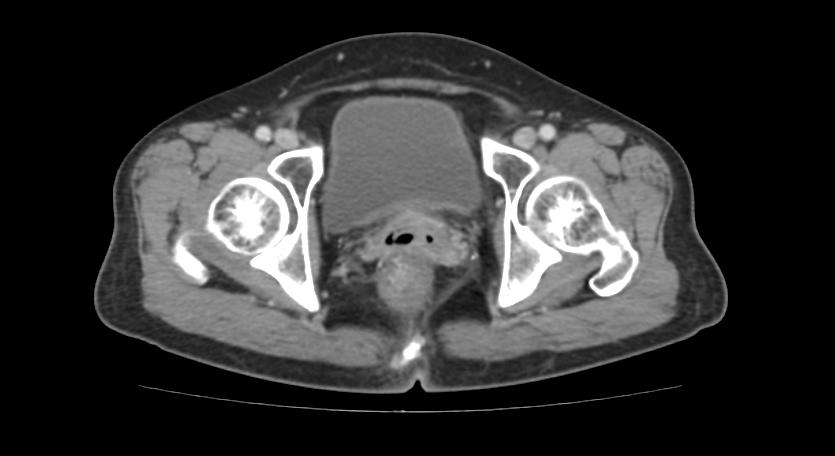

5年前我收治了一个52岁宫颈癌病人。患者已经绝经2年,出现同房后阴道流血2次,每次量约30~50毫升,患者未引起重视,无腹痛、腹胀,无尿频、尿急及尿痛,无畏寒、发热。在市妇幼保健院,完善相关检查,妇科检查病理(宫颈):“大细胞非角化型鳞状细胞癌”,CT示盆腔淋巴结转移。 考虑宫颈癌ⅡB期,收入住院。

图 1